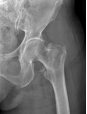

2025年11月1日,由遵义市医学会手外科分会主办、遵义市第二城市医疗集团(贵州航天医院)承办的遵义市医学会手外科分会学术交流会暨贵州省继续医学教育项目《急诊手外伤治疗临床研究新进展专题研讨班》在贵州航天医院成功举办,汇聚了遵义市手外科领域专家及基层医疗骨干,通过专题研讨与临床经验分享,共探急诊手外伤诊疗新进展。 会议特邀遵义市医学会手外科分会主任委员金文虎教授,遵义市医学会手外科分会副主任委员张子阳教授,遵义市医学会手外科分会常务委员杨绍浦教授,贵州航天医院陈明勇教授、赵兴东教授等遵义市手外伤专家进行交流分享;贵州航天医院党委委员、副院长彭亮参加会议并致辞,贵州航天医院骨科医务人员,遵义市第二城市医疗集团成员单位及红花岗区、绥阳县、桐梓县等区县医疗机构手外伤骨干参与。 贵州航天医院党委委员、副院长彭亮致辞 学术交流 本次学术交流以“急诊手外伤治疗临床研究新进展”为主题,通过理论授课与临床案例结合,共同探讨急诊手外伤临床诊疗全链条诊疗策略、关键技术、临床研究新进展,促进规范化诊疗技术向基层下沉,助力提升区域手外伤应急处置与修复能力。 贵州航天医院赵兴东教授分享《急诊手外伤的诊断与治疗原则》 贵州航天医院陈明勇教授分享《开放性骨折的治疗原则》 贵州航天医院张军教授分享《甲沟炎Winograd手术的临床应用》 贵州航天医院赵兴东教授分享《手部常见的皮肤缺损及治疗原则》 贵州航天医院张艳金教授分享《开放性骨折的清创术》 贵州航天医院冷家雄教授分享《下肢创面修复的常用皮瓣之股前外侧皮瓣》 贵州航天医院邬夏荣教授分享《踝关节慢性不稳的诊治》 贵州航天医院卢懿明教授分享《掌骨骨折》 贵州航天医院张艳金教授分享《手部肌腱的解剖与修复方法》 本次研讨班为遵义市手外科领域医务人员提供了深度交流契机,强化了医疗机构间的协作网络,进一步推动学科创新与临床实践融合,为健康遵义建设注入新动能。 贵州航天医院骨科专家简介 陈明勇 骨一科主任,副主任医师 临床擅长:从事创伤骨科工作约20年,对骨缺损、骨不连、骨肿瘤、肢体畸形等的肢体矫形重建及功能重建,慢性化脓性骨髓炎的根治治疗、糖尿病足的保肢治疗、快速康复理念(ERAS)下的老年骨折的诊治,四肢复杂骨折的诊治,四肢骨折等微创手术治疗具有丰富的临床经验。 2004年毕业于遵义医学院临床专业,曾在中国人民解放军总医院、广西医科大学第一附属医院、上海第六人民医院骨科进修。中国中西医结合学会骨伤科专业委员会横向骨搬移治疗糖尿病足及微血管网再生学组首届委员,遵义市医学会创伤分会常务委员。 瞿 晖 骨科党支部书记,骨二科主任,副主任医师 临床擅长:对骨科的常见病、关节外科、脊柱外科及运动医学疾病的诊治具有丰富的临床经验,熟练掌握骨科手术操作技术。 毕业于遵义医学院临床医学系,2005年前往广州中山大学第一附院骨显微医学部进修学习,2011年前往成都华西医院进修学习,并多次在省内外学习骨科相关知识,是中华医学会骨科分会会员。 赵小锋 中共党员,骨二科副主任,副主任医师 临床擅长:从事骨科临床工作11年,对骨科常见病、多发病诊疗有较为丰富的临床经验,擅长脊柱相关疾病诊断及治疗,尤其是颈、腰、腿疼痛疾病诊断及治疗,擅长胸腰椎骨折微创经皮穿刺内固定术、经皮穿刺椎体成形术、经皮穿刺脊柱内镜下腰椎间盘摘除术、单纯开创腰椎间盘摘除术、腰椎滑脱复位椎间植骨椎融合内固定术、腰椎管狭窄减压融合内固定术及人工髋、膝关节置换术等。 2012年毕业于遵义医学院外科学专业硕士研究生,2019年参加“遵义市115医学人才精英计划”于上海交通大学第一附属医院培训学习,2023年于北京大学第三人民医院脊柱外科进修学习,曾获得遵义市优秀医师荣誉称号。 遵义市手外科第一届委员,遵义市医学会创伤分会第一届委员,遵义市医学会创伤分会第二届委员,贵州省康复医学会第三届脊柱脊髓专业会委员,遵义市医学会烧伤与整形外科学分会委员,发表论文5篇,其中国家级核心期刊1篇,SCI论文1篇,主持市级课题1项并结题,参与市级课题2项。 赵兴东 骨科主任医师 临床擅长:擅长骨科的常见病及各种创伤、四肢骨折创伤修复、骨感染、手足疾病的诊治和手足体表畸形的矫形整复,熟练掌握骨科四肢骨病及创伤的手术操作技术,尤其在四肢关节复杂性损伤、手足外伤、组织缺损创面、难治创面的皮瓣修复方面及平足、高弓足矫形方面及四肢慢性疼痛诊治、康复方面具有丰富的临床经验。 硕士研究生,毕业于遵义医学院临床外科系,2015年前往山东省立医院手足外科进修学习;遵义市医学分会创伤分会第一、二届委员,遵义市手外科医学会第二委届员会常务委员;在省级及省级以上期刊发表文章9篇,参编著作2部,参与主持并完成市级课题1项,参与市级课题2项、省级课题1项。 张艳金 中共党员,骨科副主任医师 临床擅长:从事骨外科工作16年,对复合伤、多发伤的救治、四肢骨干骨折、关节周围骨折、骨肿瘤、骨髓炎等诊治具有丰富的临床经验。 中共党员,硕士研究生,2006年本科毕业于山西医科大学第二临床医学院,2011年研究生毕业于北京军区总医院;在“老年COPD患者合并髋部骨折的诊治”国际合作课题组研究两年,在老年髋部骨折的诊治方面具有丰富的经验,并发表论文6篇;主持遵义市级课题1项,承担遵义医科大学的临床教学工作,获得遵义医科大学优秀带教老师荣誉。编撰有《骨科疾病诊疗精粹》一书,开展2项新技术,编撰地方规范《务川自治县创伤骨科常见疾病诊疗规范》一书。 张俊凯 骨科副主任医师 临床擅长:从事骨科临床工作28年,对创伤骨折、骨感染、骨缺损、骨不连等外科诊治,四肢骨折的微创手术治疗,四肢复杂骨折(如关节内粉碎性骨折、多发骨折等)的损伤控制及手术治疗等具有丰富的临床经验。 1995年毕业于遵义医学院临床专业,2009年前往复旦大学附属医院骨科进修1年。 卢懿明 中共党员,骨科副主任医师 临床擅长:从事骨科工作18年,对创伤骨折、四肢骨折的微创手术治疗、四肢复杂骨折(如关节内粉碎性骨折、多发骨折等)的损伤控制及手术治疗,尤其是髋部骨折的PFNA等微创技术,踝关节骨折、膝关节周围骨折的Mipo微创技术等具有丰富的临床经验,开展了4项新技术,发明6项新型专利技术。 2005年毕业于遵义医学院临床专业,2017年,前往南方医科大学第三附属医院骨科进修半年,回院后运用Mipo技术对骨干骨折及干骺端骨折的治疗技术,同时积极开展骨盆骨折、髋臼骨折腹直肌外侧切口的应用;发表了多篇专业论文,经常参与省内外学术交流会授课,获得医院荣誉称号多个。 邬夏荣 骨科副主任医师 临床擅长:从事骨科工作16年,对四肢复杂骨折、骨肿瘤的诊治,尤其是足踝创伤、慢性踝关节损伤、平足症等诊疗具有丰富的临床经验。 2006年毕业于遵义医科大学临床医学专业,曾在陆军军医大学西南医院进修学习,发表多篇骨科学术论文。 余德怀 中共党员,骨科副主任医师 临床擅长:从事骨科工作10余年,对运动医学、骨关节、脊柱外科常见病、多发病的诊治具有丰富的临床经验。 硕士研究生,2011年毕业于遵义医学院临床医学专业,曾前往遵义医科大学附属医院运动医学专业进修学习;是贵州省医学会运动医学分会青年委员,西部关节镜联盟委员;发表多篇骨科学术论文。 冯 乾 骨科副主任医师 临床擅长:从事骨科工作近20年,熟练掌握骨科多发病及常见病的诊治,尤其对脊柱退变性疾病的诊断及治疗具有丰富的临床经验,主要研究脊柱微创相关治疗方式,能熟练开展椎间孔镜及UBE。 曾前往北京大学第三医院进修学习疼痛及椎间孔镜、首都医科大学友谊医院专业进修脊柱内镜;是贵州省康复医学会第三届脊柱脊髓专业委员会委员;发明专利3项、发表脊柱外科专业论文多篇。 贵州航天医院骨科简介 基本情况 贵州航天医院(原3417医院)骨科组建于1968年,前身是以创伤和断肢(断指)再植闻名于世的上海市第六人民医院骨科,中国断肢(断指)再植的奠基者、中科院院士陈仲伟等专家莅临科室指导医疗和教学,并在70年代开展了贵州省首例断肢(断指)再植手术。组建50余年来,诊治患者已逾百万,挽救了无数的伤病员,成为了保障遵义地区人民群众健康的重要支撑。 经过几代人的不懈努力,今天的骨科,已由创伤骨科发展至骨病、骨肿瘤、骨结核等领域,现有脊柱外科、关节外科、四肢创伤、手足外科四个亚专科,成为了集医疗、教学、科研于一体的综合学科,是贵州省临床重点专科、遵义市临床重点专科、遵义市骨科临床医学中心、遵义市基层骨科专科联盟理事长单位。 科室目前开放床位110张,共有医护人员50余人,副高级以上专家18人,硕士研究生15人。拥有一流骨科医疗设备多台,每年不定期选派优秀技术骨干到全国各大知名医学院校进修、学习、参观、交流,并邀请国内、国外知名专家教授来院进行交流、指导,通过不断引进国内外先进的诊疗技术,科室医疗技术水平稳步提升,为广大人民群众提供了优质的医疗服务。 专科特色 骨一科 (一)骨缺损、骨不连的肢体与功能重建 胫骨横向骨搬移技术治疗糖尿病足: (二)慢性骨髓炎的根治治疗 (三)肢体缺血性疾病如糖尿病足、脉管炎的保肢治疗 (四)皮瓣修复 (五)复杂创伤的治疗 (六)老年髋部骨折及小儿骨折快速手术 老年髋部骨折: 骨二科 (一)胸腰椎骨折微创经皮椎弓根螺钉固定术 (二)老年性骨质疏松性患者腰椎滑脱脊柱内固定术(骨水泥螺钉) (三)V形双通道脊柱内镜技术(VBE)腰椎融合术治疗腰椎退行性疾病 (四)老年性骨质疏松性骨折(PVP/PKP)术 (五)人工髋关节置换术 (六)双侧股骨头坏死人工全髋关节置换 (七)右侧全髋置换术后假体周围骨折翻修 (八)人工膝关节置换术 (九)人工膝关节假体松动翻修 (十)关节镜技术 传统手术切口 关节镜技术切口 诊疗范围 骨一科 1.四肢创伤、矫形。 2.手、足踝外科。 骨二科 End